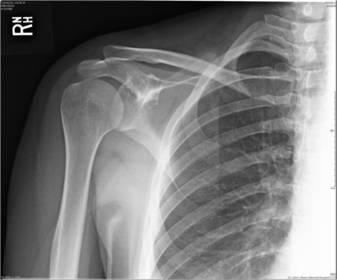

| Scapular Y-Lateral | ANATOMY: humeral head resting in the 'Y' of the acromion and coracoid process CRITERIA: vertebral border and lateral border of scapula are directly superimposed humeral head is aligned with body of scapula POSITIONING: pt's unaffected arm is abducted 90 degrees, pt in 45-60 degree anterior oblique CR perpendicular @ scapulohumeral joint (neer) CR angled 10-15 degrees caudal @ scapulohumeral joint |

| Inferosuperior Axial Shoulder | ANATOMY: lateral view of the proximal humerus in relation to the glenoid fossa CRITERIA: lesser tubercle in profile medially humeral head is in the center of VOI POSITIONING: affected arm abducted 90 degrees, hand rotated externally with hand supinated CR horizontal 25-30 degrees medial to the scapulohumeral joint |

| Posterior Oblique Grashey | ANATOMY: glenoid cavity in profile glenohumeral joint center of VOI CRITERIA: open glenoid cavity anterior/posterior rims of glenoid cavity are superimposed POSITIONING: pt in 35-40 degree posterior oblique CR perpendicular @ glenoid cavity |